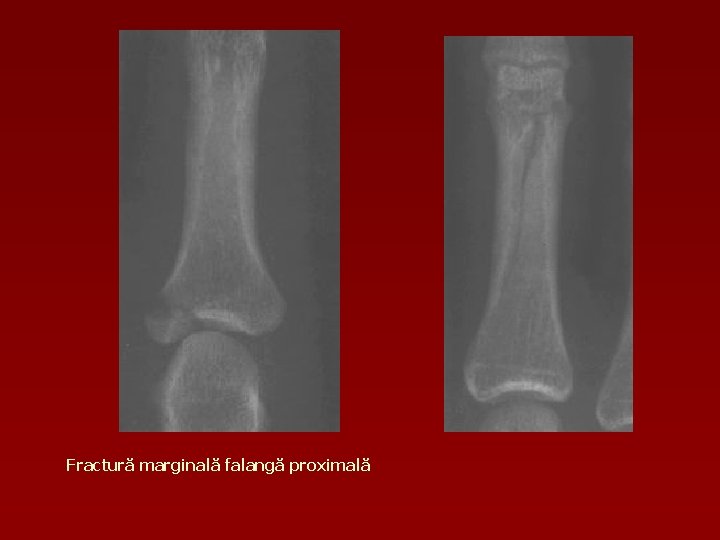

Fractură marginală falangă proximală